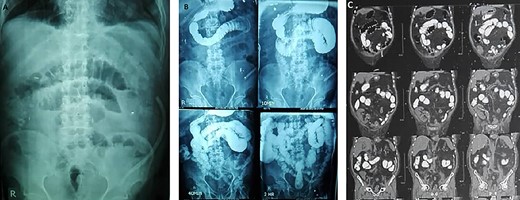

A 71-year-old man, who had received renal transplantation 10 years ago, presented with bladder tumor. Transurethral resection of bladder tumor revealed muscle-invasive BCa. After refusing surgery, he received chemotherapy. Due to no response to chemotherapy, he was referred to us. In primary evaluation, serum creatinine was 1.9 mg/dl (glomerular filtration rate (GFR) = 37 ml/min/1.73m2). Computed tomography (CT) scan revealed mild-to-moderate hydronephrosis of transplanted kidney and two small and atrophic native kidneys with no evidence of tumor metastasis (Fig. 1). In cystoscopy, a 5–6-cm sessile mass was detected in the right bladder wall with involvement of transplanted ureter orifice. Trans-urethral resection of the tumor was performed, and pathologic evaluation revealed high-grade urothelial cell carcinoma with muscularis propria involvement. After counseling, the patient decided to undergo RC.

Preoperative CT scan shows mild-to-moderate hydronephrosis in transplanted kidney and two atrophic native kidneys.